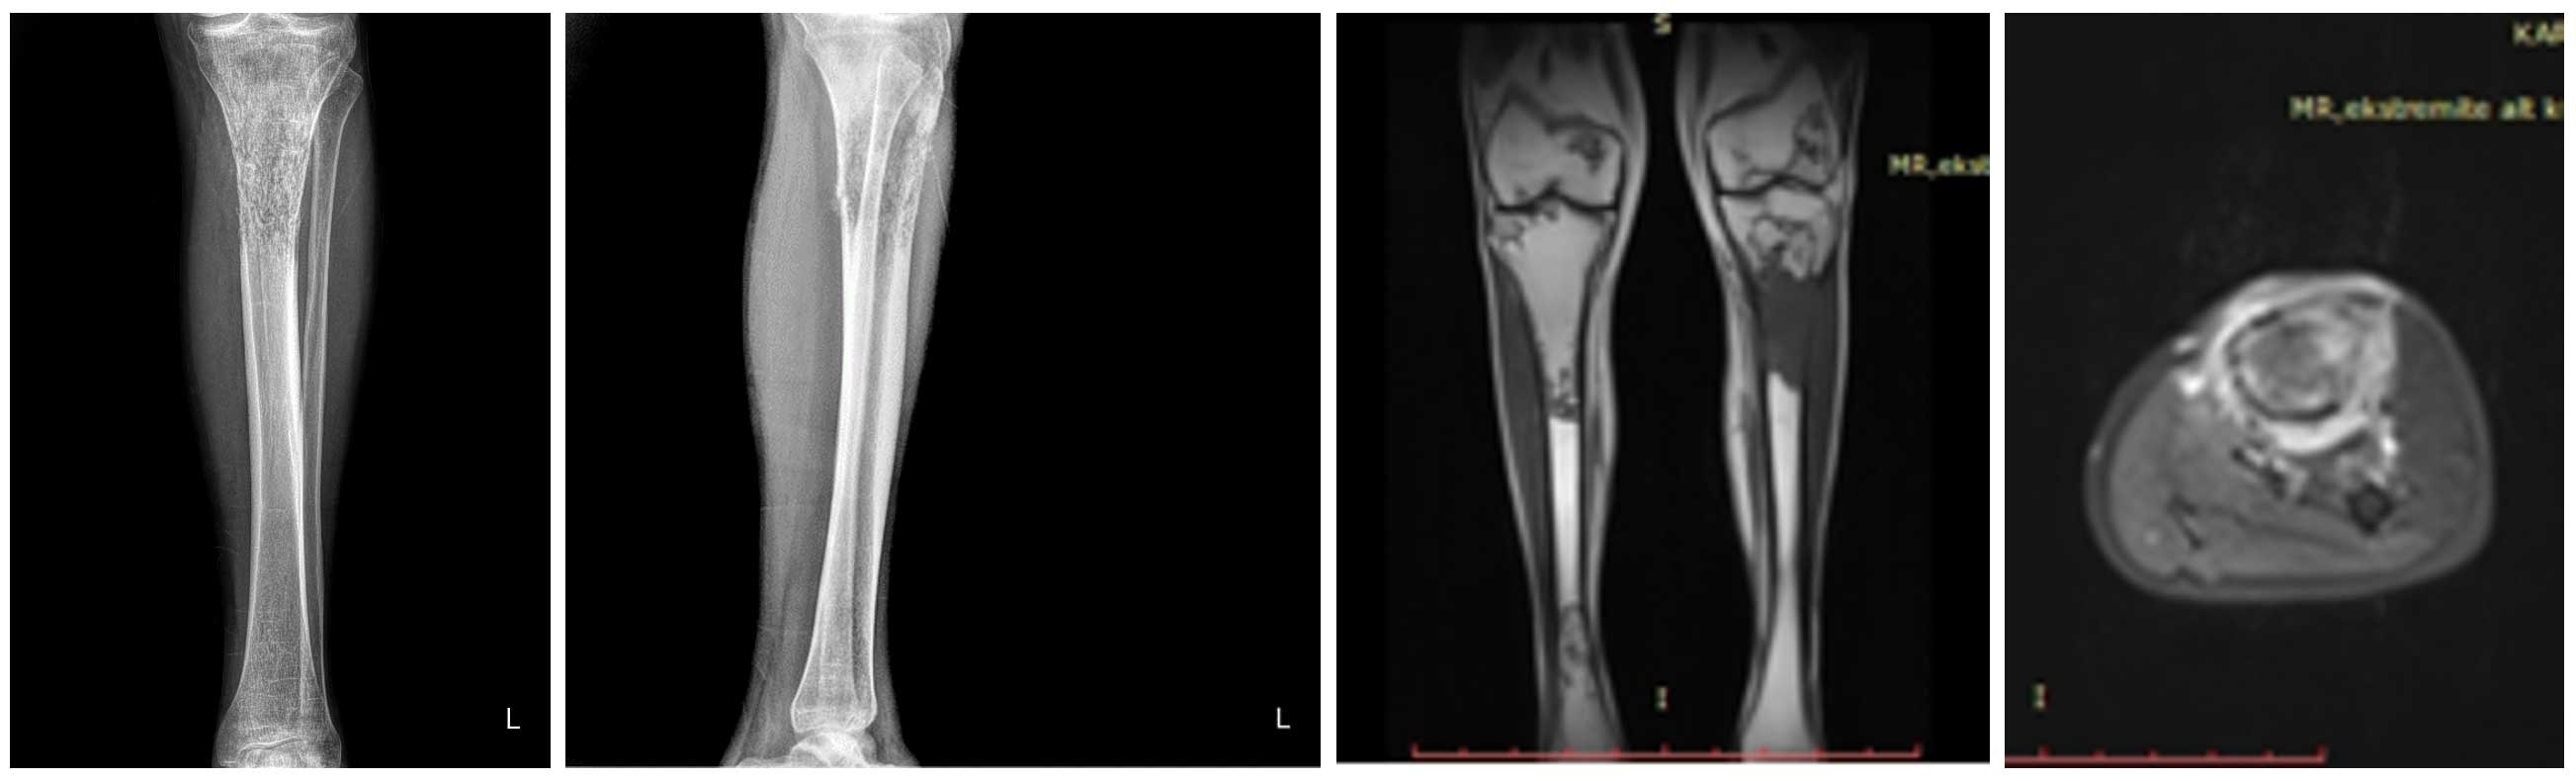

Görüntülemelerde sol tibia (kaval kemiği) üst uçta akciğer kanseri metastazına bağlı belirgin kemik zayıflığı saptandı ve patolojik kırık riski yüksek olarak değerlendirildi.

Ameliyat Öncesi: Röntgende sol tibia üst uçta kemikte harabiyet ve ayrışmamış kırık, MR’da aynı bölgede tümör dokusu ve çevreleyen ödem görülmekte.